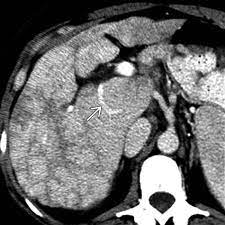

Chiasmata -mə-tə or chiasmas also chiasms 1. Esophageal varices are extremely dilated sub-mucosal veins in the lower third of the esophagus. Located in metro Denver northern Colorado and western Nebraska serving all of the Front Range our team consists of board-certified and fellowship-trained interventional radiologists. This results in hepatic congestion similar to Budd-Chiari syndrome and post-sinusoidal portal hypertension. The patients condition should be monitored throughout the procedure. They are most often a consequence of portal hypertension commonly due to cirrhosis. Toxic injury to liver sinusoids causes sloughing of endothelial cells that embolize to hepatic venules and cause eventual fibrosis of the venules. Coin in the Esophagus. There is no clear consensus regarding the number of occluded veins some authors claim that there should be at least one occluded hepatic vein 7 others state that there are no significant.

Carcinoma of the Colon. Budd-Chiari syndrome a blockage in one or more veins that carry blood from the liver back to the heart. And coumarin skin necrosis adrenal gland hemorrhage and infarction. Toxic injury to liver sinusoids causes sloughing of endothelial cells that embolize to hepatic venules and cause eventual fibrosis of the venules. Chiari malformation CM is a structural defect in the cerebellum characterized by a downward displacement of one or both cerebellar tonsils through the foramen magnum the opening at the base of the skull. Embolism and thrombosis of. La présence dune ou plusieurs affections prothrombotiques est fréquente La prise en charge repose sur un traitement anticoagulant précoce le traitement de l.